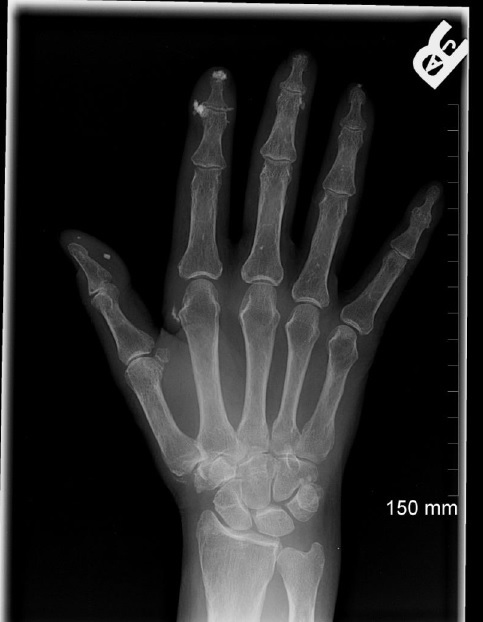

tophi (gout)